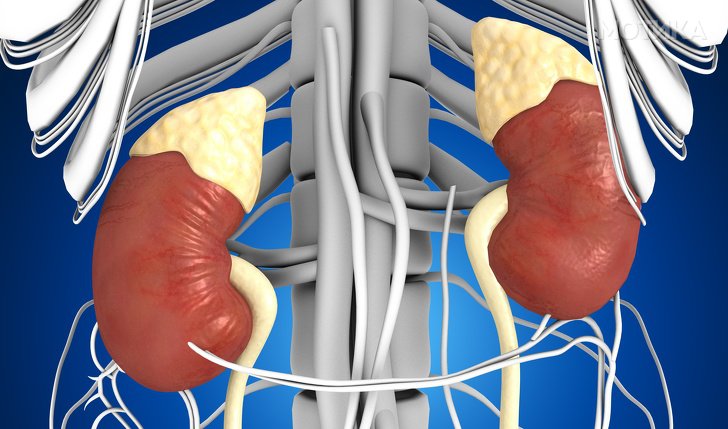

4. Бубрези

- Главната функција на бубрезите е да се прочисти крвта од отпадни производи. И за да успее во тоа, секој поединечен бубрег има најмалку еден милион и до 2 милиони специјални мали филтри, наречени нефрони.

- Навистина не ни требаат 2 бубрези, половина од една може да завшри исто толку добра работа како 2.

- Ако детето е родено со само еден бубрег, тоа ќе се здебели до тежината на 2 бубрези.

5. Надбубрежни жлезди

- Тие го ослободуваат хормонот за стрес- адреналин. Адреналинот пренесува сигнали до мозокот за сите потенцијални опасности, а потоа мозокот му помага на нашето тело да се подготви за реагирање.

- Ако произведува премногу андрогенски стероиди, тоа може да доведе до високи машки карактеристики, како што е ќелавост и повеќе влакна на лицето и за жените и за мажите.